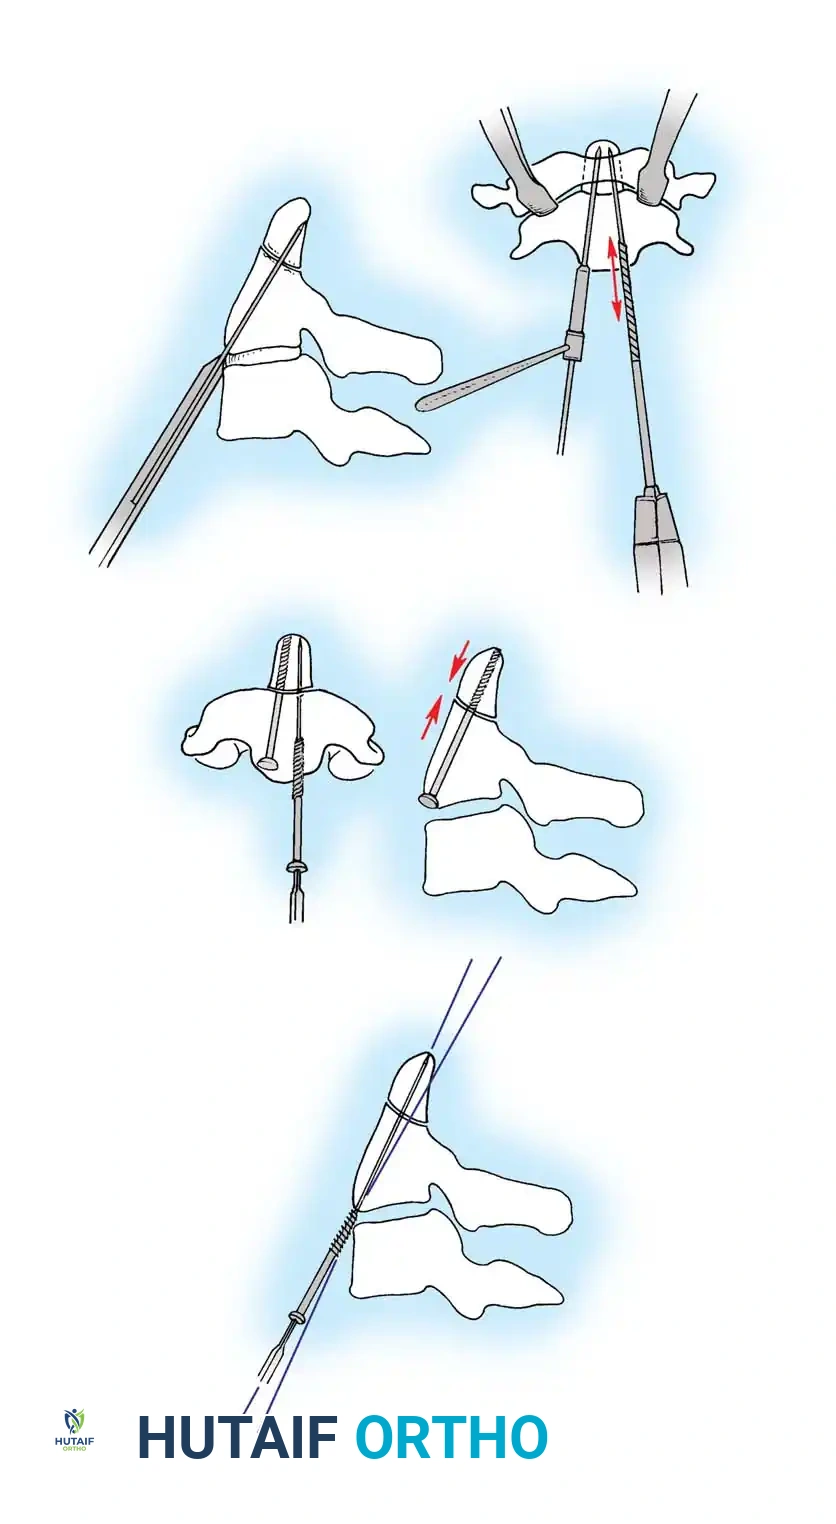

Surgical Steps:

1. Open Reduction: If a facet is dislocated, carefully lever the inferior articular process of the superior vertebra over the superior articular process of the inferior vertebra using a Penfield elevator.

2. Lateral Mass Screw Fixation:

* Utilize the Magerl or Roy-Camille trajectory.

* Magerl Technique: The entry point is 1 mm medial and 1 mm superior to the center of the lateral mass. The drill is angled 25 degrees laterally (to avoid the vertebral artery) and 15 degrees cephalad (to avoid the exiting nerve root).

3. Rod Contouring: Contour titanium or cobalt-chrome rods to match the patient's natural cervical lordosis and secure them to the screw heads with set screws.

4. Decortication and Fusion: Aggressively decorticate the lateral masses and facet joints with a high-speed burr. Pack the gutters with cancellous autograft (often harvested from the iliac crest) or high-quality allograft.